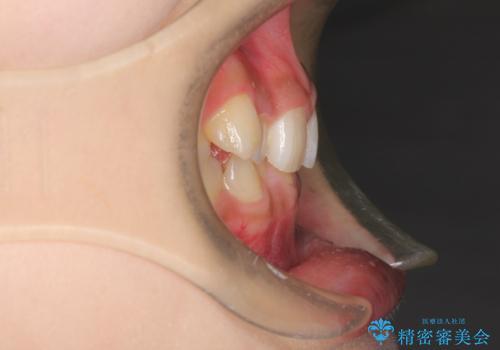

- 前歯のガタガタを主訴に来院された患者様です。

八重歯になっており、下顎の前歯が上顎の前歯に隠れてしまう、ディープバイトという状態でした。

インビザラインを使用して矯正する計画としました。

ディープバイトの場合、ワイヤー装置の装着が難しいことがあります。

インビザラインではかみ合わせに左右されず装着できるメリットがあり、ワイヤーに比べインビザラインの方が治療しやすい場合もあります。